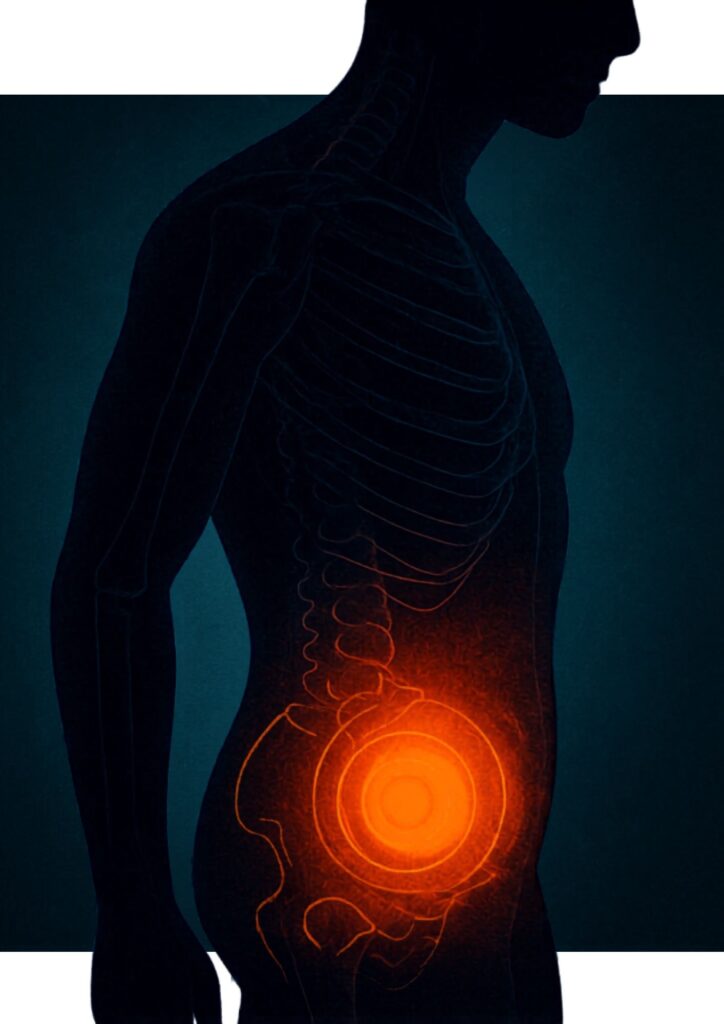

Jake 在節目中提到,很多人一聽到盆底肌,第一時間會聯想到產後女性;但其實男士同樣有盆底肌,而這組肌肉與排尿控制、膀胱支援、核心穩定,以至部分性功能表現都有關。

男士進行盆底肌練習(Kegel exercise)有助膀胱控制。不過,真正困難的地方往往不是「知唔知要練」,而是「你究竟知唔知自己有冇用啱力」。

以往女性使用的盆腔置入式電子感應和電剌激訓練儀, 其生理結構不適合男仕使用,但近年發展的HIFEM儀器,隔著衣物便能引發骨盆底肌群收縮,可以幫助使用者更容易感受肌肉收縮與控制模式,讓訓練不再抽象,也令男士有一個更有效途徑作盆底功能改善,協助應對控制力與夜尿問題。